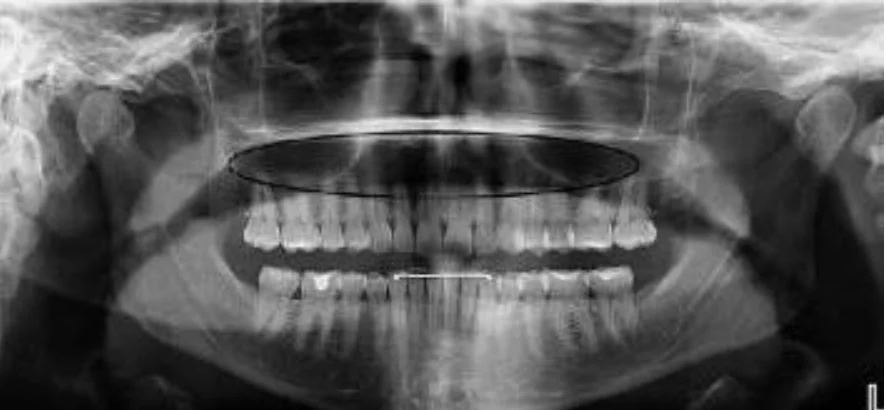

Dark area occluding maxillary apices

This is probably one of the most common problems we see with busy offices taking panoramic images. However, this symptom can be tricky to get rid of.

The most common root cause of this artifact is the patient failing to hold their tongue flat against the top of the hard palate. While most operators are aware of this recommended step, there are two additional lesser-known facts that may thwart dental professionals trying to remove this artifact from their images.

First, simply telling the patient to “put your tongue to the top of your mouth” may not solve this problem. The reason for this is that many patients may take this direction to mean they should simply touch the roof of their mouth with the tip of their tongue. This approach will not solve this problem because the goal is to remove the air gap between the tongue and the hard palate. Instead, we recommend that the operator should instruct the patient to “press the tongue flat against the roof”, which will better remove the air gap that can cause this artifact.

Another challenge for the office is that there is a very similar-looking artifact that may present for a completely different reason. If a large cross sectional area of the hard palate is between the x-ray source and the mandibular apices, this can absorb x-rays exposing this region, and can result in the dark artifact. This can be caused if the occlusion of the patient is “too flat”. The ideal approach to avoid this is to position the patient with a slight (~10 degree) downward tilt of the occlusal plane.